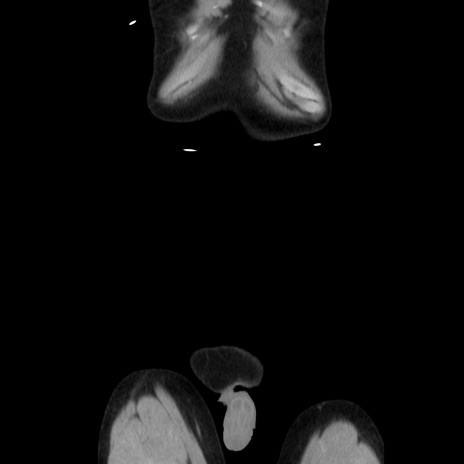

横断像